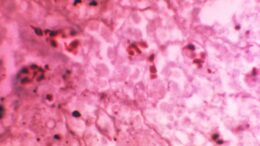

Clusters of microscopic bacteria exist all around us. These invisible communities, known as biofilms, are found in habitats ranging from our skin surface to sewer pipes and play integral roles…